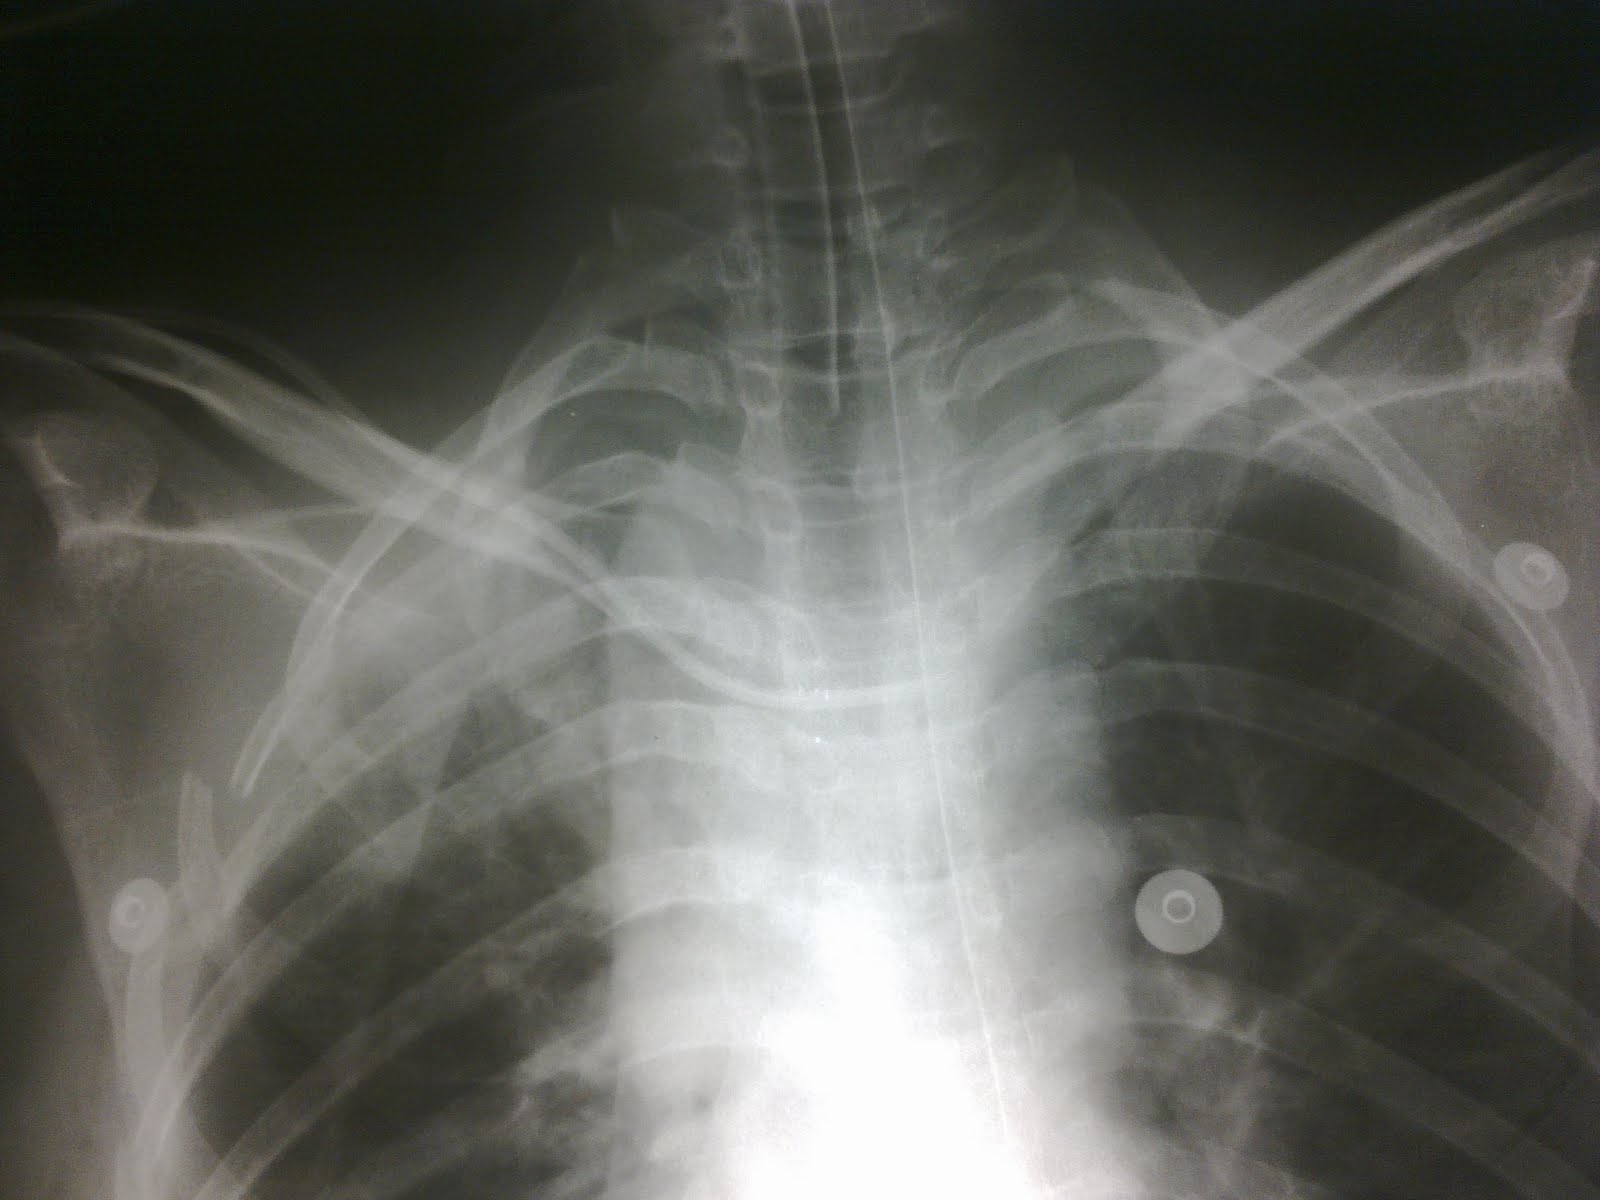

Chest radiography for simplified evaluation of central venous catheter